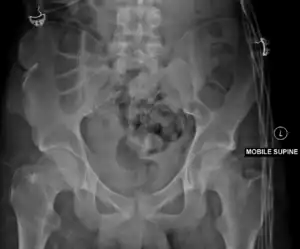

| Malgaigne's fracture | Joseph-François Malgaigne | vertical pelvic fracture through both pubic rami and the ilium or sacroiliac joint with vertical displacement | high energy impact to pelvis (front to back) | Malgaigne's fracture Archived 2017-11-02 at the Wayback Machine at TheFreeDictionary.com | |